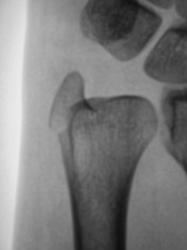

Пациент направлен врачом общей практики (ВОП) на рентгенографию лучезапястного сустава с диагнозом "Перелом?". Произведено стандартное исследование лучезапястного сустава. Выявлен перелом лучевой кости в типичном месте почти без смещения отломков, перелом локтевой кости в области основания шиловидного отростка с незначительным смещением отломков по ширине. Возникает подозрение на разрыв дистального луче-локтевого сочленения. Ваше мнение коллеги?